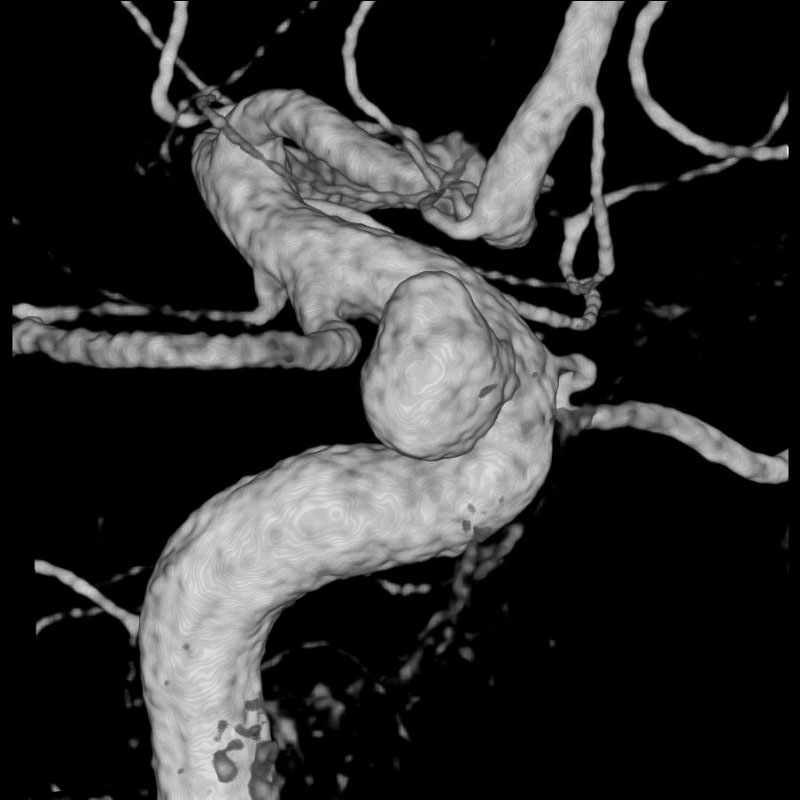

脳動脈瘤(Rt.IC)

フローダイバーター留置術

須山/松田/濵田

脳動脈瘤(Lt.IC-PC)

脳血管内手術

芝野/古谷/木本

脳動脈瘤(Lt.VA-PICA)